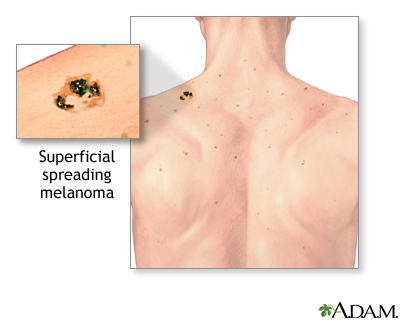

- Superficial spreading melanoma is the most common type. It is usually flat and irregular in shape and color, with different shades of black and brown. It is most common in fair skin people.